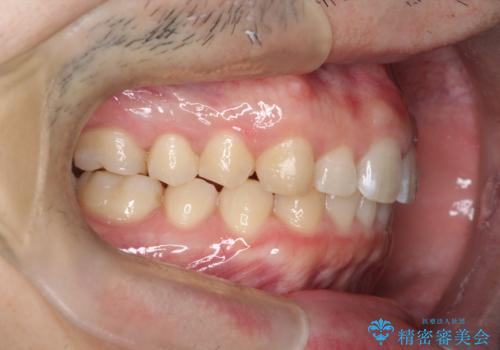

治療途中に転勤されて、簡単にはお越し頂けなくなり、来院頻度が少なくなってしまいましたが、しっかり使っていただけたことで計画通り歯を動かすことができました。